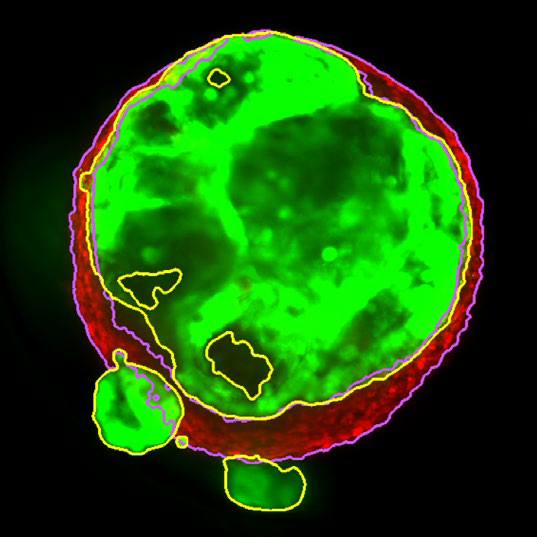

MaxIP image of 3D tumor co-culture microtissue - NCI-N87-GFP (gastric carcinoma; green) and NIH-RFP (murine fibroblast; red)

Figure 2. MaxIP image of 3D tumor co-culture microtissue - NCI-N87-GFP (gastric carcinoma; green) and NIH-RFP (murine fibroblast; red). Image Credit: Yokogawa Life Science

Z slice of the tumor microtissue treated with 0.05% DMSO - tumor (yellow region) and fibroblast (purple region) are recognized separately in 3D

Figure 3. Z slice of the tumor microtissue treated with 0.05 % DMSO - tumor (yellow region) and fibroblast (purple region) are recognized separately in 3D. Image Credit: Yokogawa Life Science

Z slice of the tumor microtissue treated with 5 μM Lapatinib - tumor (yellow region) is decreased significantly comparing to the one treated with 0.005% DMSO

Figure 4. Z slice of the tumor microtissue treated with 5 μM Lapatinib - tumor (yellow region) is decreased significantly compared to the one treated with 0.005 % DMSO. Image Credit: Yokogawa Life Science

Outcome

Tumor spheroids were created by seeding an Akura 384 plate with a monodispersed mixture of GFP-expressing NCI-N87 (gastric carcinoma) and RFP-expressing NIH3T3-L1 (murine fibroblast) cells, which spontaneously formed spheroids through scaffold-free self-assembly over several days. After spheroid formation, selected wells containing tumor spheroids were treated with DMSO at 0.05, 0.5, or 5.0 μM Lapatinib for six days. The images were analyzed in 3D, with NCI-N87-GFP (tumor) and NIH-RFP (fibroblast) identified separately, and the volume of each spheroid measured.